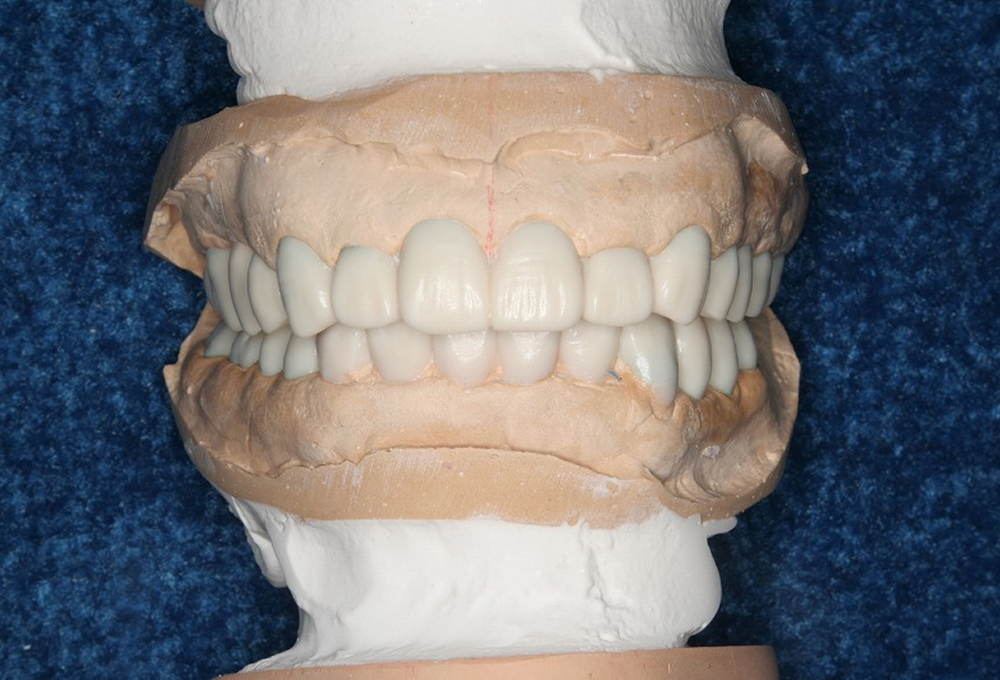

②診断用ワックス模型